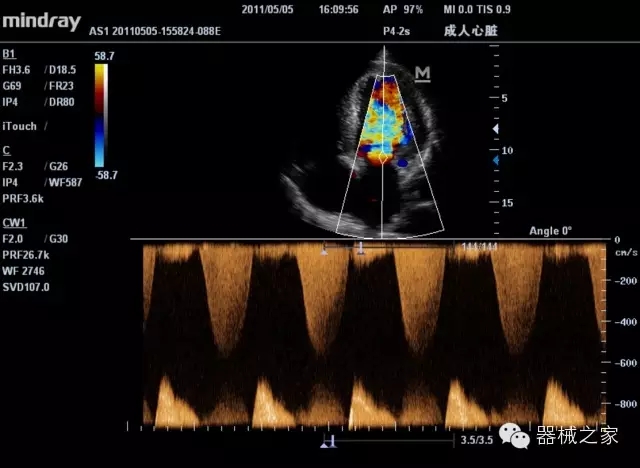

經(jīng)典產(chǎn)品:M7(星鉆)

臨床圖片賞析

產(chǎn)品特點(diǎn)

·裝載有采用Multi-Core多核處理的非嵌入式平臺(tái),成像效率大大提高,并且能夠給用戶帶來高速、多任務(wù)并行信號(hào)處理體驗(yàn);

·優(yōu)秀的圖像效果、強(qiáng)大的功能體驗(yàn)、豐富的探頭選擇、合理的便攜式設(shè)計(jì),全中文顯示及病人管理界面,使得M7在任何場(chǎng)合、任何時(shí)候都能快速響應(yīng)更好的心血管、腹部、婦產(chǎn)、小器官等常規(guī)超聲檢查以及肌骨、神經(jīng)、顱腦、術(shù)中等新興領(lǐng)域的使用需求;

8倍波束并行處理系統(tǒng)

·在便攜式緊湊平臺(tái)上采用更多倍波束并行接收信號(hào)處理模式,無論二維還是彩色血流圖像狀態(tài)下,擁有更靈敏的回波頻移捕獲能力,大大提高時(shí)間分辨率,尤其使得心血管表現(xiàn)更為突出;